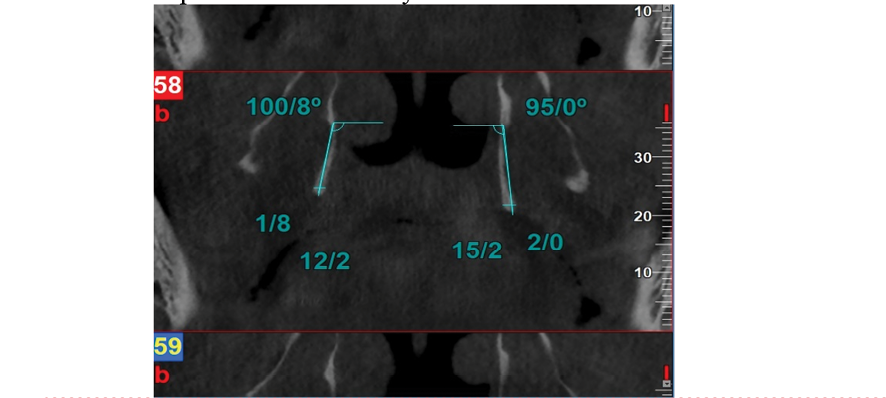

The images embedded on NNT software were examined by two oral and maxillofacial radiology specialists on a 14-inch LED flat monitor (ASUS, 1920 × 1080 resolution) in a semi-dark room using the NNT software. The observers were able to view the images in both axial and coronal planes. If necessary, contrast and brightness were adjusted by the observers. The size of the hamulus (length and width) at its thickest and longest point in the coronal sections was measured using a digital ruler in the NNT software. Additionally, the inclination of the projection in the coronal plane relative to the base of the sphenoid at the separation of the pterygoid plates, as well as in the axial plane, was measured at the same location in the most distinct section. The length and width of the pterygoid hamulus at its longest and thickest point in the coronal sections, as well as the sagittal and coronal plane inclinations of the pterygoid hamulus, were measured by both observers using a digital ruler. The results obtained were then provided to a statistical expert for further analysis. The data in this study were analyzed using SPSS software version 22 (SPSS 22 for Windows, SPSS Inc., Chicago, IL). Initially, descriptive statistics methods including frequency distribution tables, charts, and measures of central tendency and dispersion were used to describe the variables under study. To test the normality of the distribution, the Shapiro-Wilk test was applied. Given that the data followed a normal distribution, ANOVA and T-test were used. A significance level of P≤0.05 was considered for all statistical tests.

Figure 1. A sample of CBCT images taken in the coronal section